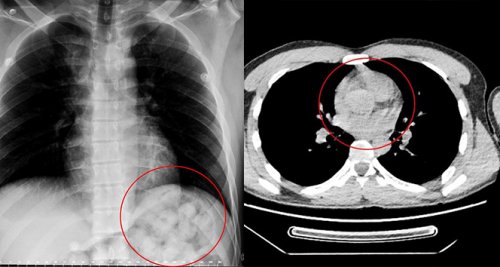

Edinilen bilgiye göre, 5 gün önce Van'dan otobüsle Ankara'ya gelen O. Zahed Ahmed Narziveh rahatsızlanınca hastaneye kaldırıldı. Ankara Şehir Hastanesine getirilen şahsın röntgen görüntüleri gerçeği ortaya çıkardı. Şahsın midesinde 890 gram ağırlığında 2'si patlamış halde 72 kapsül olduğu ve kapsüllerin patlaması ile fenalaştığı belirlendi. Mahkeme kararına istinaden ameliyata alınarak midesindeki metamfetamin kapsülleri çıkartılan zanlı, Ankara Emniyet Müdürlüğüne bağlı Narkotik Suçlarla Mücadele ekiplerince hastanedeki 5 günlük tedavisinin ardından adliyeye sevk edildi.